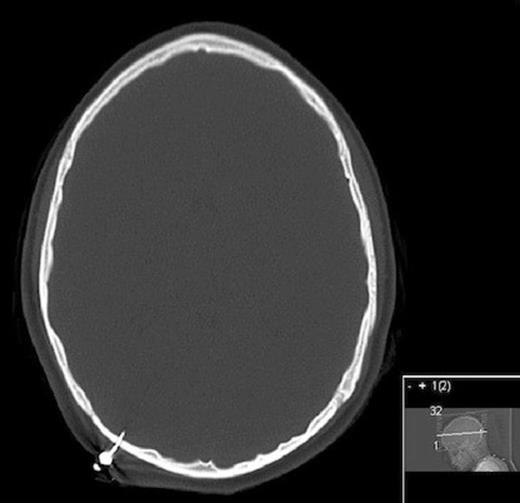

No hemorrhage was noted. The transverse sinus was not involved. Multiple attempts were made at removing the TASER dart under sterile conditions at bedside with the dart subsequently breaking, leaving only the intracranial component (Figure 3).

After attempt at removing dart at bedside in patient two, extracranial portion broke off